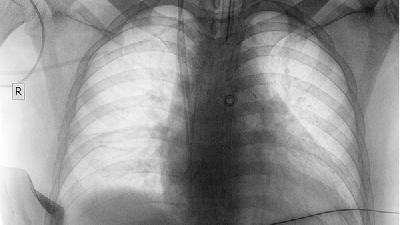

判斷肺癌早期、中晚期或晚期的檢查辦法,了解腫瘤的大小、部位、侵及范圍、有無侵及周圍組織器官、有無肺外其他臟器的轉移,這就是我們常講的肺癌臨床分期。由于肺癌容易發(fā)生顱腦轉移、骨轉移和腹腔臟器轉移,治療前除外和確定有無肺外轉移對醫(yī)生和患者都至關重要。

臨床上我們經(jīng)常會遇到這樣的病例,病人胸片和胸部CT發(fā)現(xiàn)肺部孤立性結節(jié)陰影,經(jīng)氣管鏡活檢確診是肺癌,胸外科醫(yī)生馬上就給病人"成功地"實施了肺切除手術。自認為預后良好的病人,很短時間后就發(fā)現(xiàn)肺外有多發(fā)轉移,如顱腦、肝臟、骨骼等部位的轉移,事實上這些病人在手術前就已經(jīng)出現(xiàn)了肺外轉移,只是因為沒有例行檢查、沒有發(fā)現(xiàn)而已。如果術前作了腹部超聲、顱腦核磁共振、全身骨掃描等檢查,就能夠及早發(fā)現(xiàn)肺外轉移,從而使病人避免開胸手術而選擇其他的治療手段